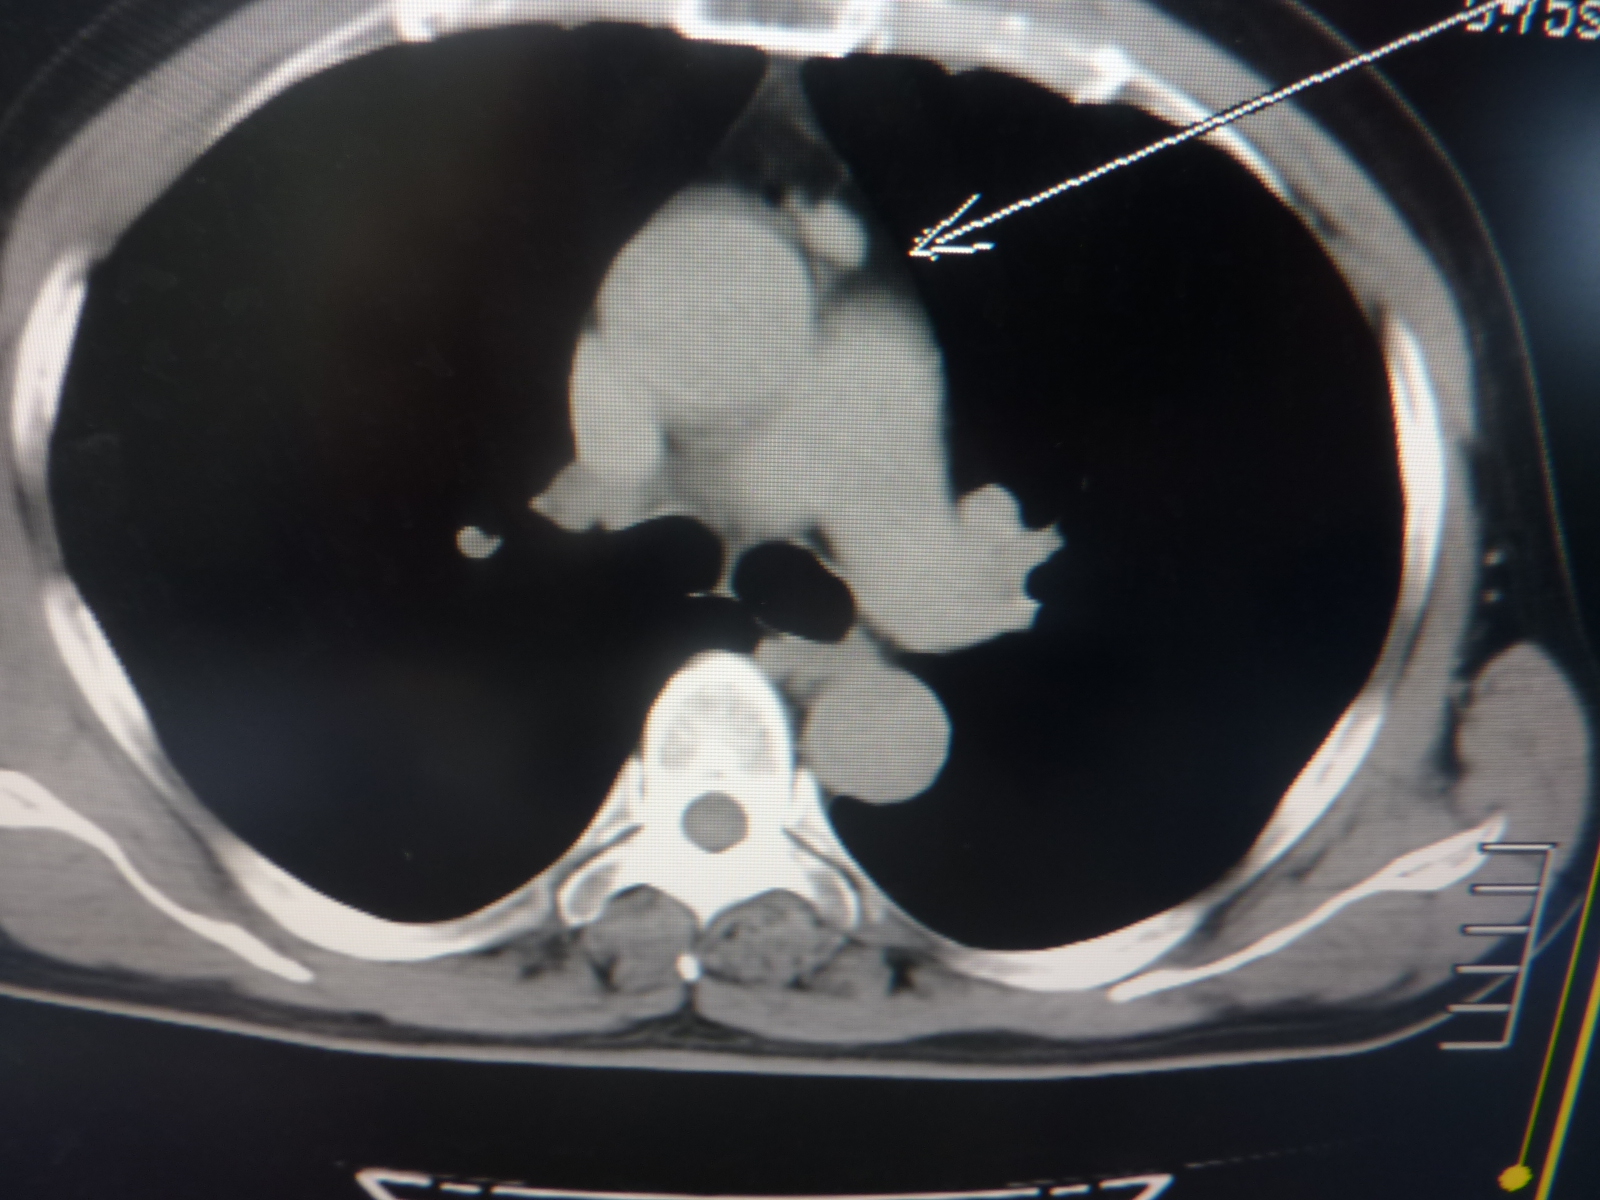

CT53226:感冒咳嗽半月

前纵隔结节灶是胸腺瘤?右肺中叶慢性炎症

前纵隔结节影,考虑未退化胸腺,建议结合临床。

右肺中叶内侧段斑片结节状密度增高影,提示炎症可能。心前区升主动脉邻近结节。考虑:血管影可能。建议增强。

建议增强